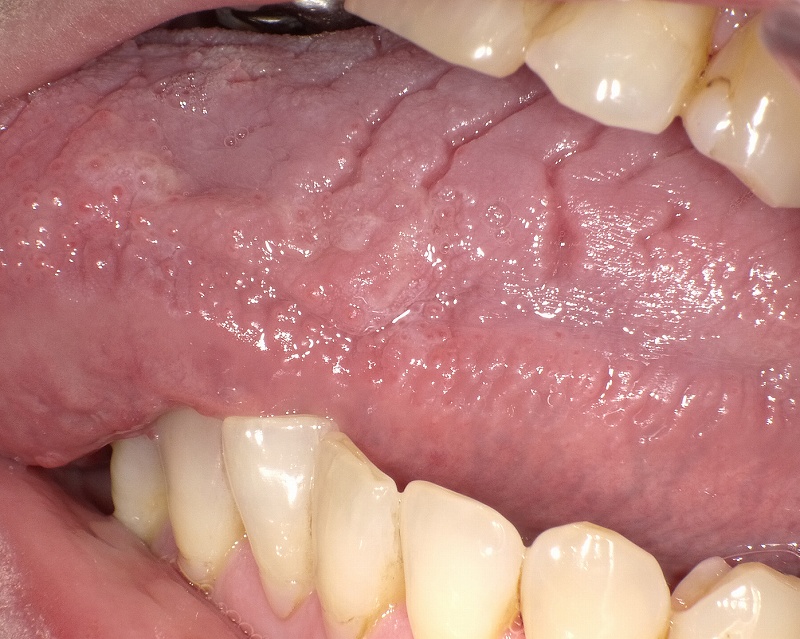

溝状舌。

溝状舌 - のぼる君の歯科知識。

溝状舌 こうじょうぜつ とは 溝状舌の痛みの原因と対処法。

溝状舌 こうじょうぜつ について – 吉祥寺 歯医者 – さくま歯科。

舌に溝がある これって大丈夫?溝状舌の正体と対応法。